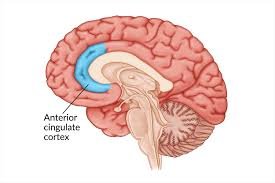

The role of the anterior cingulate cortex

One structure deserves particular attention: the anterior cingulate cortex (ACC). Research consistently shows that it is strongly activated during hypnotic induction, and its activation appears to facilitate the neuroplasticity that makes hypnosis therapeutically effective.

The ACC is considered the brain’s centre of desire and the will to act. It is also central to the experience of pain and emotion. Under hypnosis, its activation contributes to a heightened sense of depth, better emotional regulation, and increased suggestibility — the brain’s willingness to respond to therapeutic suggestions.

Notably, the ACC is the region that stops functioning in cases of akinetic mutism or catatonia. Its role in hypnosis helps explain why the hypnotic state can access and influence experiences — including pain, automatic responses, and emotional memory — that are difficult to reach through conscious effort alone.

Absorption, the capacity to become fully immersed in an inner experience while external perceptions fade into the background, is associated with increased activity in the executive control network and with the hyperfocused attention of the anterior cingulate cortex and fronto-parietal networks. It is not a passive state. It requires active neural engagement.